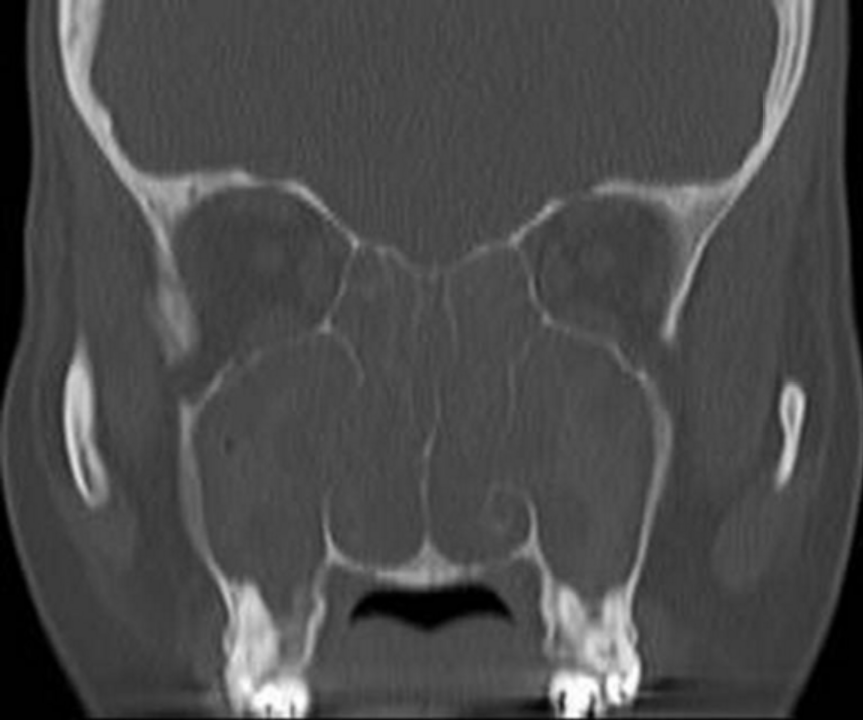

Endoscopic signs include nasal polyps , mucopurulent discharge (primarily from the middle meatus), and mucosal edema (also primarily in the middle meatus). CT findings include mucosal thickening of the paranasal sinuses and osteomeatal complex and fluid or debris in the paranasal sinuses (opacification).

A fungus ball (mycetoma) is a collection of inspissated fungal debris and mucus in an isolated paranasal sinus. Symptoms are similar to CRS or patients can occasionally be asymptomatic. The maxillary sinus is the most common location. Characteristic CT appearance is a heterogeneous hyperdensity within a sinus with microcalcifications. Intraoperatively, fungal balls appearing as a mass of thick, crumbly debris and fungal hyphae are often appreciable. Treatment is endoscopic removal, and antifungal medications are not typically required.